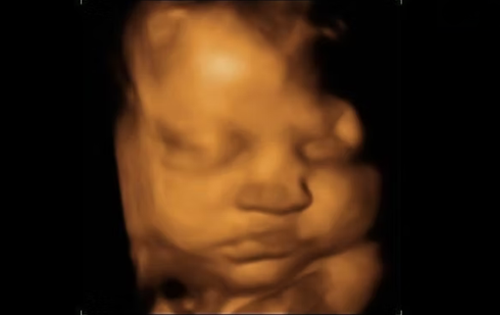

Advanced ultrasound, screening, and diagnostic services for accurate fetal and maternal health assessment.

Performing the scan requires skill and concentration. So the doctor may be quiet for short periods of time which is entirely normal. After the initial test and measurements are complete, the baby will be shown to the expecting parents and explained.